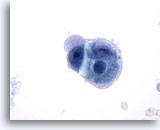

画像 1: 肝FNA – 良性肝細胞 良性肝細胞の小さな集塊。細胞は多角形のものもあれば円形のものもみられ、細胞境界は明瞭です。 核は中心性に位置し、周辺の細胞質は顆粒状を呈しています。細胞質内に色素沈着がみられます。小型の核小体がみられるものの、異型性および高N/C比は認められません。

60倍

画像 1

肝FNA – 良性肝細胞

良性肝細胞の小さな集塊。細胞は多角形のものもあれば円形のものもみられ、細胞境界は明瞭です。 核は中心性に位置し、周辺の細胞質は顆粒状を呈しています。細胞質内に色素沈着がみられます。小型の核小体がみられるものの、異型性および高N/C比は認められません。

60倍